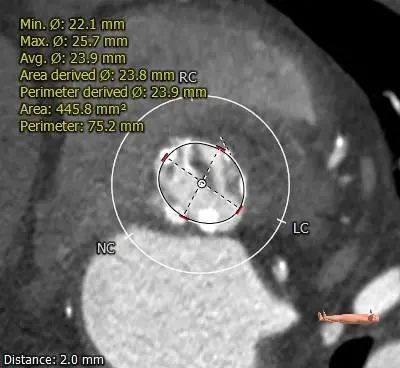

ANNULUS

2mm SUPRA ANNULUS